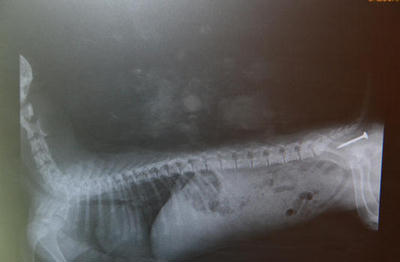

Ciało obce w przełyku.